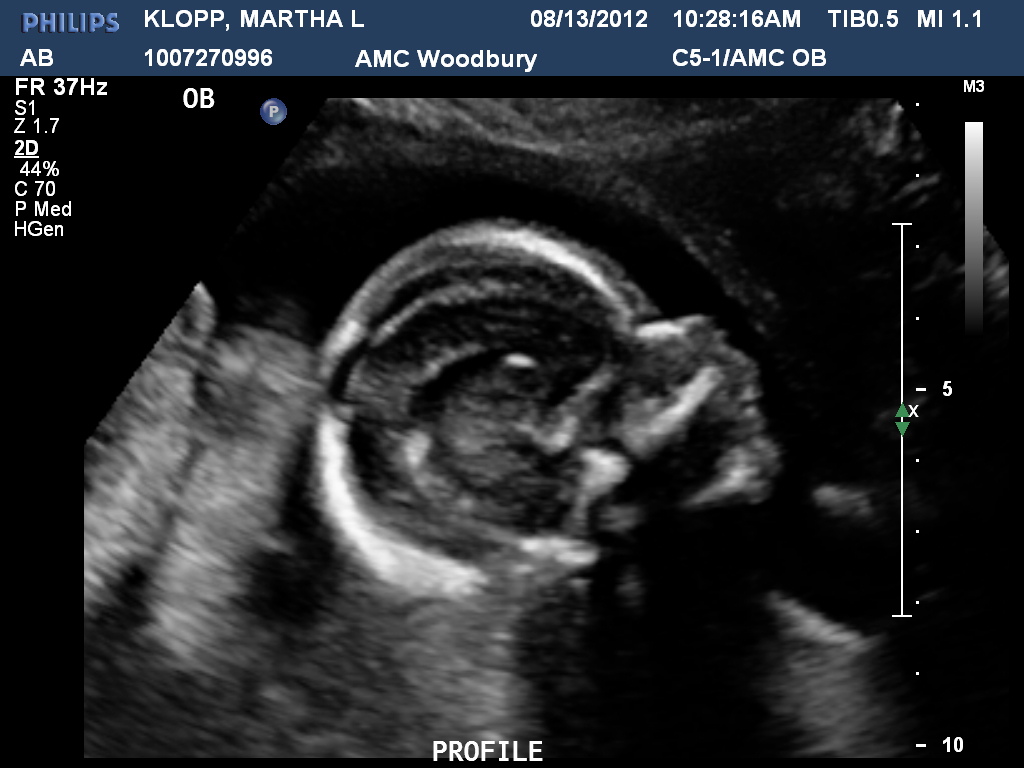

BOY! And he's healthy! He was measuring 20 weeks exactly (I'll be 20 weeks on Wednesday) and everything on the anatomy scan looked normal. Dan couldn't be there for the ultrasound so I had the tech write it in the envelope. I called Dan after the ultrasound and before the OB routine appointment, and he said "Just open it now!" (We were going to wait and skype tonight.) We are both so excited...it's almost too perfect. I hope everything continues this smoothly.

| Baby Boy Klopp |